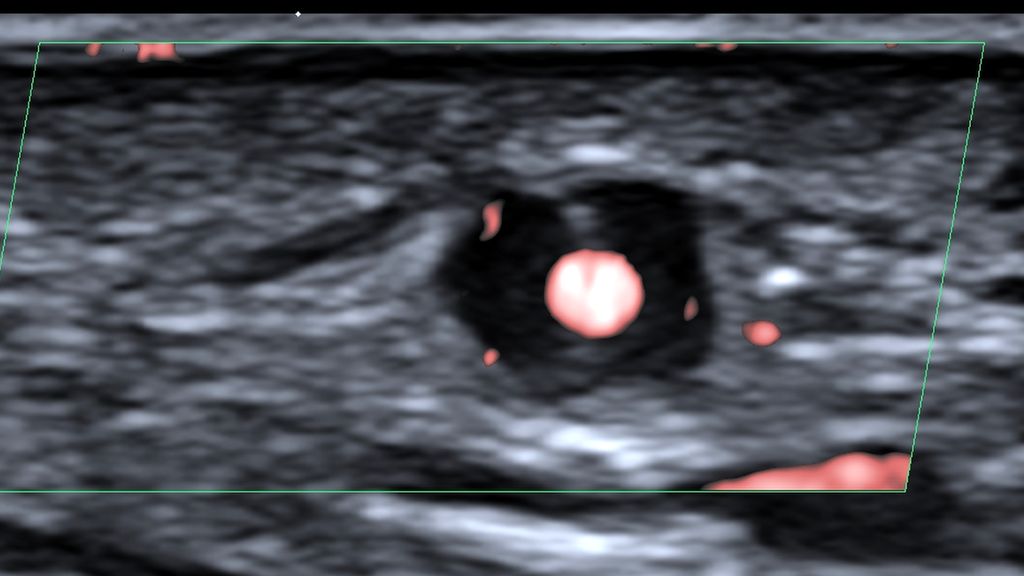

In einer Pilotstudie wurden Patienten mit Riesenzellarteriitis mit Tocilizumab behandelt und das Prednisolon wurde über nur 8 Wochen ausgeschlichen statt wie sonst üblich über 6 Monate.1 Ein Großteil der Patienten war damit auch noch nach einem Jahr in Remission. Ob diese kortikoidsparende Therapiestrategie Zukunft hat, müssen nun randomisierte Studien zeigen.

Lange Zeit waren Glukokortikoide die einzige Therapieoption für eine Riesenzellarteriitis. Seit der Zulassung von Tocilizumab im Jahr 2017 steht den Patienten nun eine wirksame Behandlung zur Verfügung, die Kortikoide einspart. Leider gehen 6 Monate einer Prednisonbehandlung immer noch mit diversen Nebenwirkungen einher, von denen manche schwerwiegend sind. Forscher von der Harvard Medical School haben nun in einer Pilotstudie untersucht, ob es auch reicht, nur 8 Wochen lang Kortikoide zu geben.1